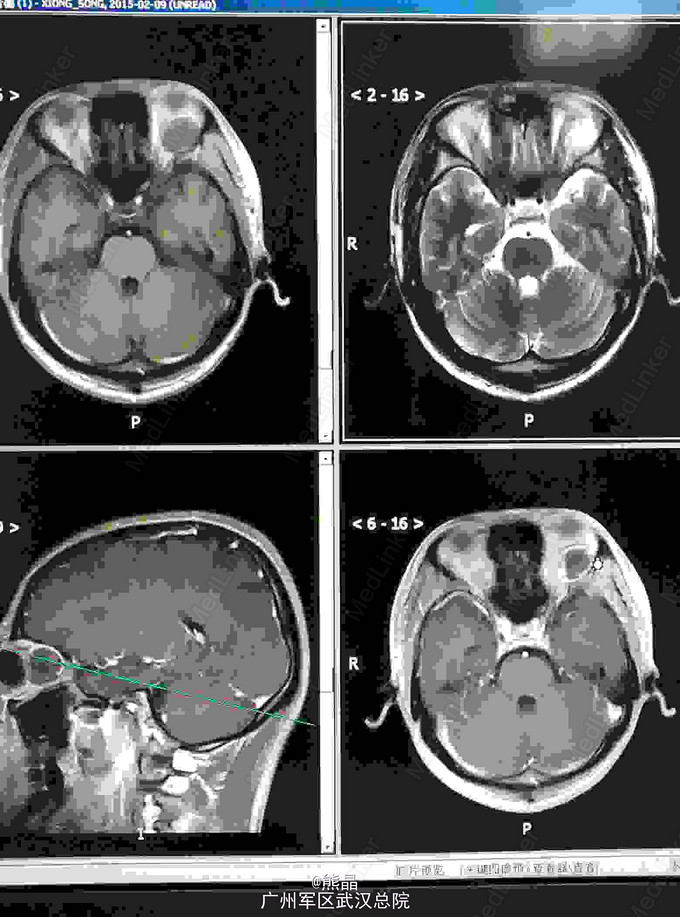

左眼眶神经鞘瘤的MRI表现一例

男性患者,27岁,左眼球突出2月余

MRI表现:左眼眶内球后肌锥内可见一椭圆形等T1长T2信号,内可见液平,增强呈斑片状强化,余未见明显异常

本院手术,术后病理,神经鞘瘤